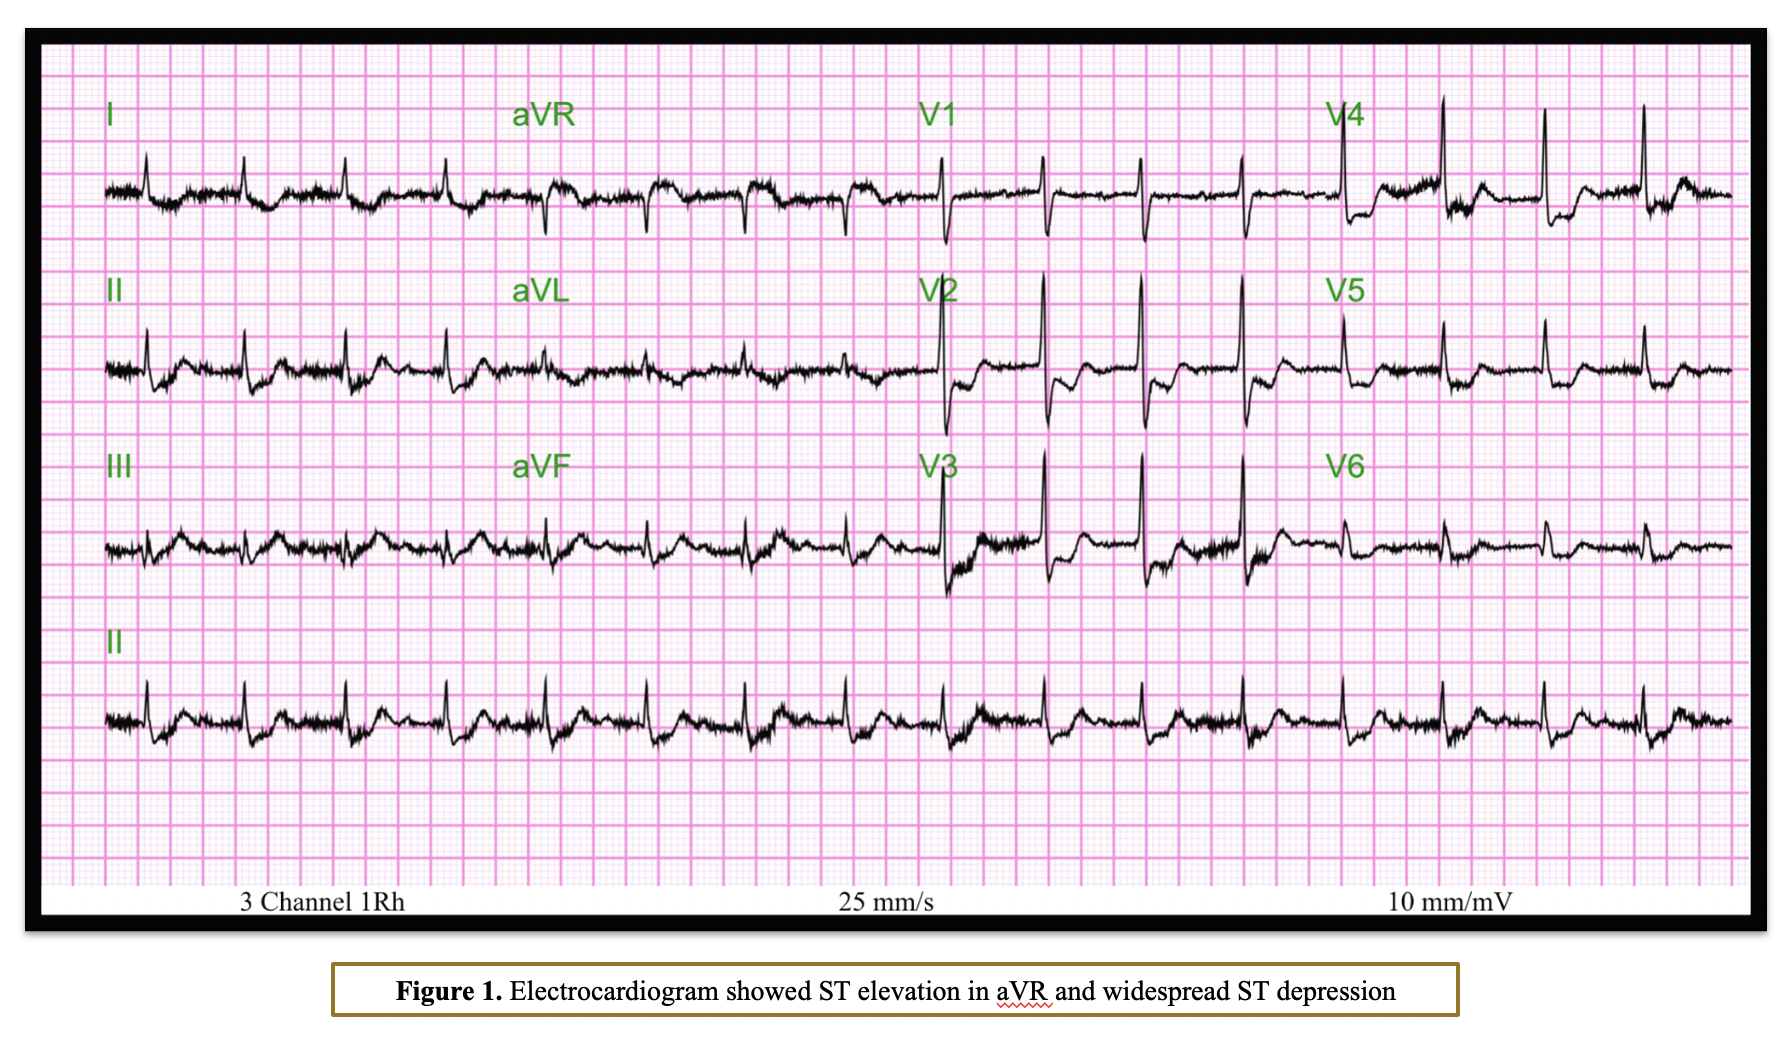

An 81-year-old male presented to the emergency department with NSTEMI and cardiogenic shock. His past medical history included hypertension, type II diabetes, peripheral vascular disease, and CKD stage IV (estimated glomerular filtration rate [eGFR] 17 mL/min/1.73 m©÷). An electrocardiogram (ECG) showed ST elevation in aVR and widespread ST depression.